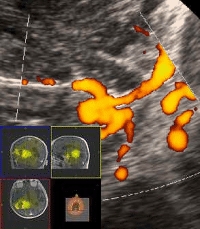

Die Ultraschalldiagnostik in der Neurochirurgie ist eine bewährte Methode um Befunde, auch präoperativ, schnell und schonend aufzufinden. Besonders intraoperativ können krankhafte Gewebsveränderungen im Hirngewebe oder des Rückenmarks direkt, während des Eingriffes frühzeitig erkannt und entfernt werden. |